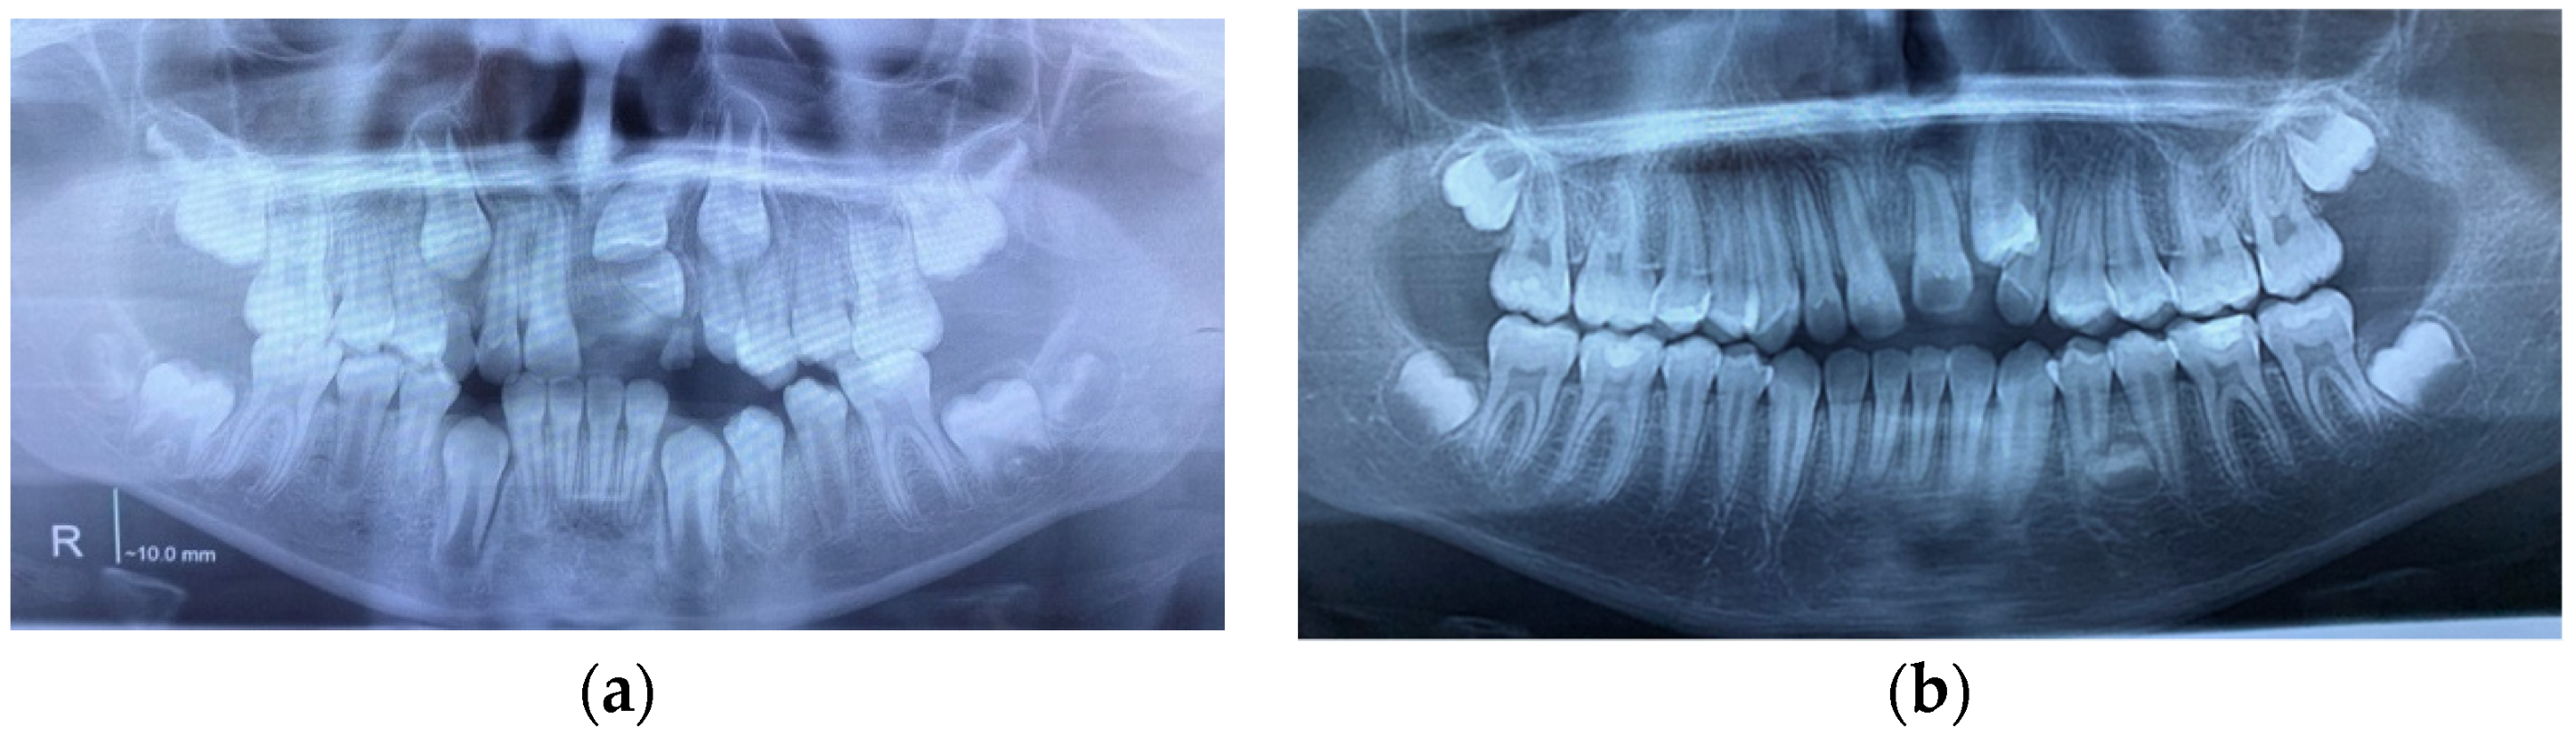

| Case Number | Summary of X-ray Findings |

| Case 1 |

|

| Case 2 |